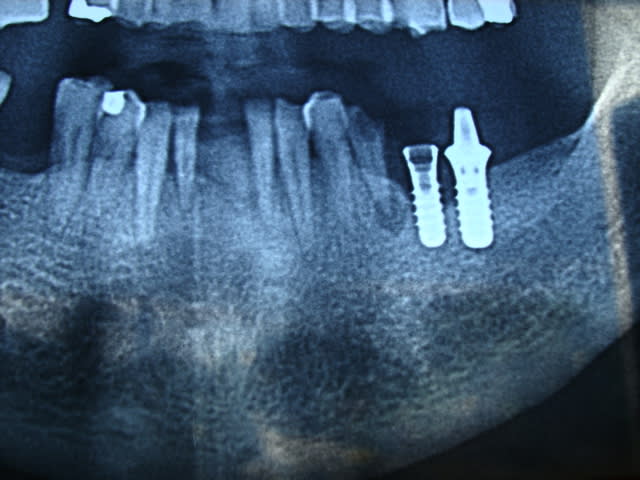

bon comme tout le monde seche, je vous mets quand même une radio

l'engin se prénomme tissue level Straumann...ou un clone...difficile d'être plus précis avec cette pano...

reste que la connexion est un octogone....

Yes, Staumann ou clone, mais au final, c'est out ( avec les dents du bas) et all-on sur nouveaux implants ...